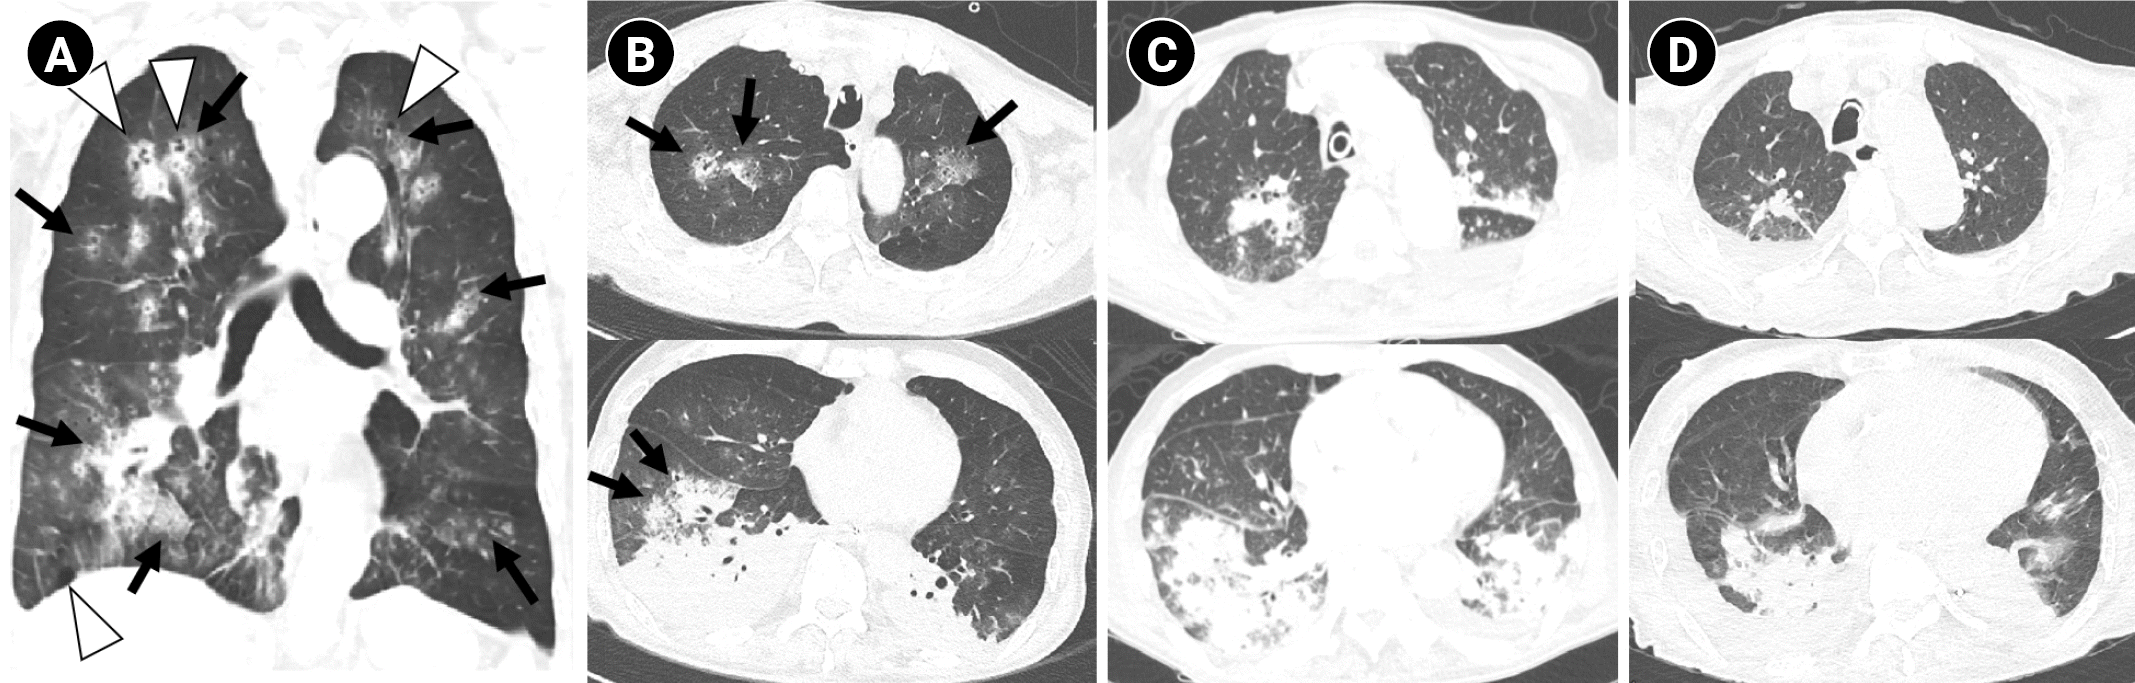

An 85-year-old man with a history of carotid artery stenosis, hyperlipidemia, chronic kidney disease, and dementia was admitted to the intensive care unit (ICU) because of sputum produced 1 day prior and worsening dyspnea on the visit day. Upon admission, the patient was drowsy, with blood pressure 69/37 mm Hg, heart rate 75 beats/min, respiratory rate 22 beats/min, body temperature 36.9 °C, and pulse oxygen saturation 60% at room air. Coarse breath sounds with crackles were heard in both lung fields. Concurrent with mechanical ventilation, adequate intravenous fluid and norepinephrine were administered. The initial serum lactate level was elevated to 2.5 mmol/L. Chest radiograph showed increased opacities mainly in the right lower lung field (Figure 1A). Chest computed tomography revealed multifocal nodules with surrounding ground-glass opacities (GGOs), the “halo sign” in underlying emphysematous lungs, and extensive consolidation with GGO in both lower lobes (Figure 2A and B). The initial white blood cell and absolute neutrophil counts were 3,110/μl and 2,430/μl,, which increased to 8,430/μl and 6,830/μl on the second day, respectively. Non-specific erythematous bronchial mucosa with a large amount of thick, purulent sputum was observed on bronchoscopy, and bronchial lavage and culture were performed. Serum high-sensitivity C-reactive protein (hs-CRP) and procalcitonin levels were 16.47 mg/dl and 20.9 ng/ml, respectively. The broad-spectrum antibacterial agent cefepime was infused immediately. During the first 5 days, the blood platelet count decreased markedly from 103,000 to 65,000 /µl; serum creatinine level increased from 1.7 to 2.0 mg/dl; and serum hs-CRP and procalcitonin levels increased to 18.07 mg/dl and 55.0 ng/ml, respectively. The initial bronchoscopic culture and respiratory virus multiplex tests showed negative results, except the galactomannan (GM) antigen level from bronchoscopic washing was elevated at 1.5. The serum GM antigen level was also elevated at 4.99 (Figure 3). Blood beta-D-glucan (BDG) level peaked at greater than 1,000.0 pg/ml. With suspicion of invasive aspergillosis, oral voriconazole was added on the third day of admission. The patient was not at high risk for multidrug-resistant organism infection related to recent exposure to antimicrobial drugs or hospital admission and was not at high risk for opportunistic infection due to immunosuppression. Ten days later, given that the hs-CRP level was still high at 16.06 mg/dl and the follow-up chest CT images revealed aggravation of nodular consolidations, oral voriconazole was replaced with intravenous liposomal Amphotericin B (Figure 2C). The hs-CRP level finally improved to 3.80 mg/dl 1 week after start of intravenous liposomal Amphotericin B. Finally, Aspergillus fumigatus was cultured on the 33rd day from the endotracheal aspirate sample collected on the 26th day of intensive care. The patient was weaned from the mechanical ventilator on the 40th day of ICU admission in the tracheostomy state and discharged from the ICU after 45 days of intensive care. The follow-up radiograph and CT images showed partial improvement of nodular consolidations (Figure 1B and 2D).

Figure 1.

(A) The initial chest radiograph shows increased opacities, mainly in the right lower lung field. (B) The last chest radiograph on the 74th day of admission reveals decreased opacities compared to (A).